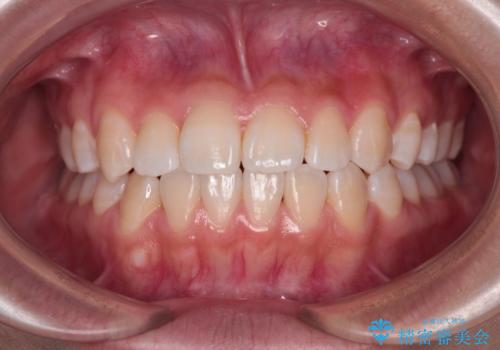

前歯のデコボコを楽して改善 ワイヤー装置による矯正治療

- 治療期間

- 1年2ヶ月